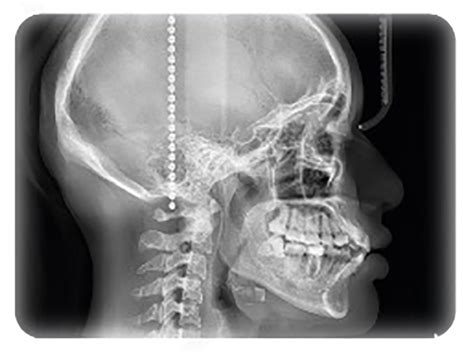

Dentro del proceso del diagnóstico, el análisis cefalométrico es una técnica indispensable para el éxito del caso. La cefalometría es una técnica radiográfica utilizada en ortodoncia para medir y analizar las relaciones dentoesqueléticas y faciales de un paciente. En este análisis, se utilizan puntos anatómicos de referencia que se encuentran en las estructuras óseas y dentales, los cuales se identifican en las radiografías y se utilizan como puntos de partida para realizar las mediciones pertinentes. Estos puntos de referencia incluyen el nasion, el punto A, el punto B, el punto pogonion, entre otros.

- Radiografía cefalométrica: Esta radiografía se utiliza en ortodoncia para evaluar la relación entre las estructuras óseas de la cabeza y la cara.

Las radiografías cefalométricas son esenciales para evaluar la relación entre los huesos y las estructuras faciales, lo que permite a los ortodoncistas comprender la posición de los dientes y la mandíbula. Otro tipo de radiografía dental que puede ser solicitada de forma previa al tratamiento de la ortodoncia es la radiografía panorámica, que ofrece una vista completa de todas las estructuras dentales en una sola imagen.

El cefalostato es un dispositivo esencial en la radiología dental, especialmente en el campo de la ortodoncia. Su función principal es mantener la cabeza del paciente completamente inmóvil durante la toma de radiografías cefalométricas. Gracias a sus apoyos auriculares y nasales, permite al profesional dental obtener una imagen lateral o frontal del cráneo en una posición exacta y reproducible.

En ortodoncia, el cefalostato es una herramienta clave. Permite obtener radiografías laterales del cráneo que son fundamentales para realizar estudios cefalométricos. También es muy útil para planificar tratamientos como la colocación de brackets o alineadores, y para hacer un seguimiento riguroso de la evolución del paciente.